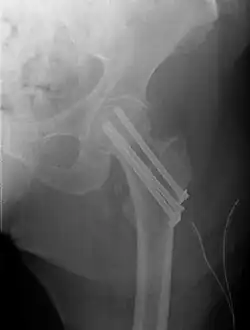

Fracture treated with cannulated screws

For low-grade fractures (Garden types 1 and 2), standard treatment is fixation of the fracture in situ with screws or a sliding screw/plate device. This treatment can also be offered for displaced fractures after the fracture has been reduced.

Fractures managed by closed reduction can possibly be treated by percutaneously inserted screws.[38]